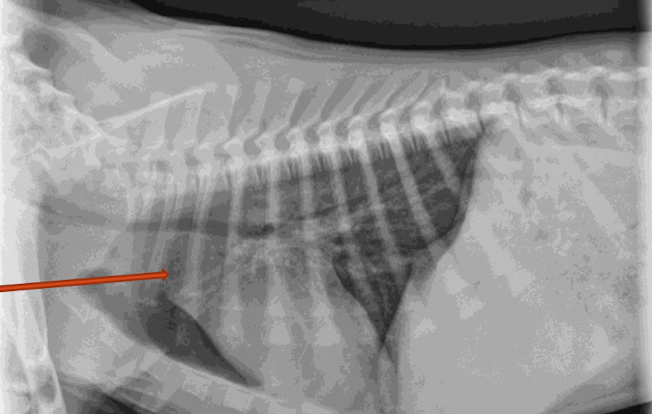

What is the arrow pointing to?

intra-capsular swelling